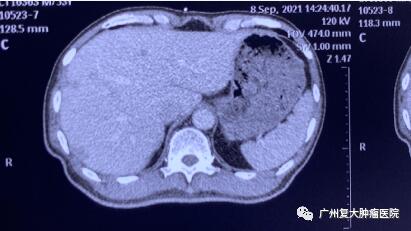

为求进一步诊疗,2020年11月,患者来广州复大肿瘤医院就诊。入院完善相关检查发现:CA-199指标高达2289u/ml(CA-199属胃肠道肿瘤相关抗原,是一种肿瘤标志物,正常值≤37u/ml);肝实质内有多个结节状,较大者约4.3×3.8cm。胰腺体、尾部均有肿块,并邻近肠管、脾静脉局部粘连不清,大小约4.3x3.3cm。

影像图片显示

图1